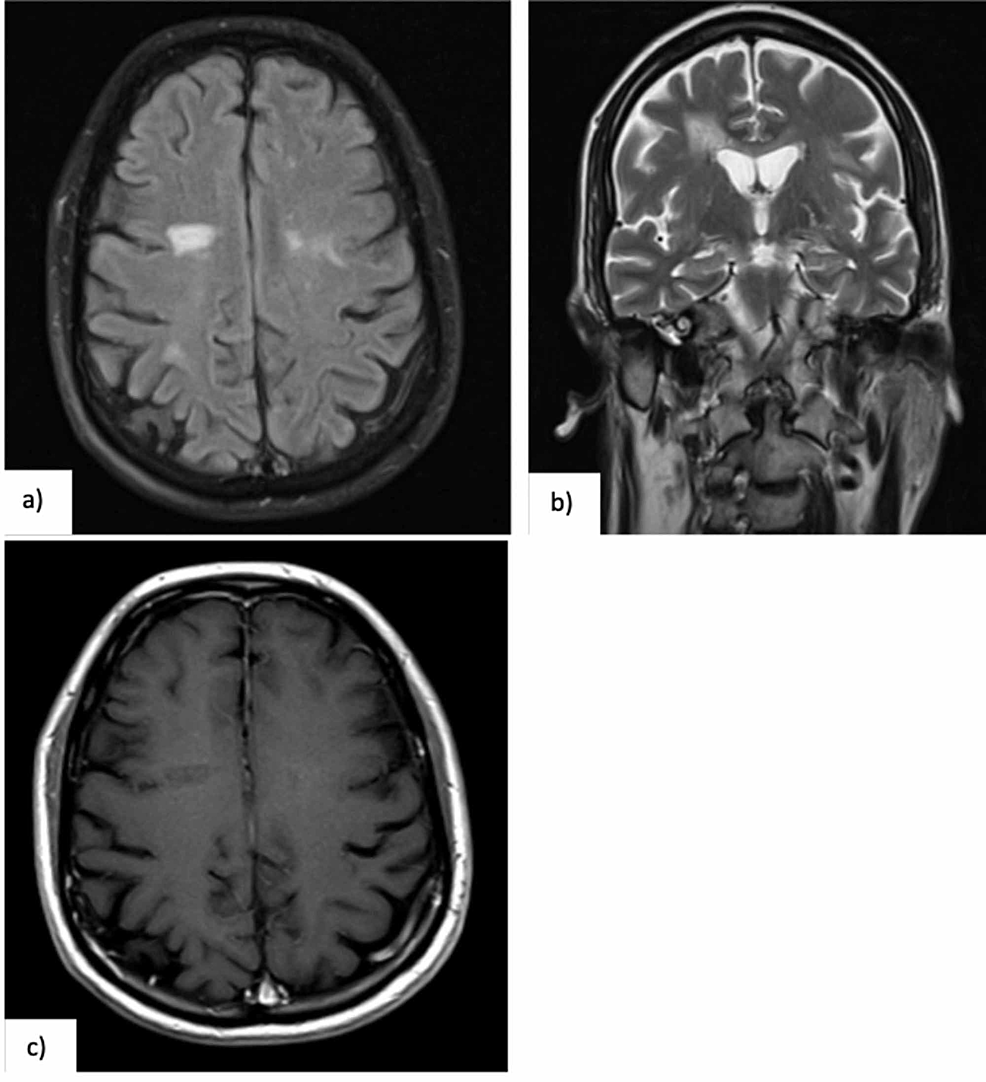

MRI brain without contrast showing nonspecific white ...

MRI brain without contrast showing nonspecific white ... from www.researchgate.net

Usually the lesions of brain are insignificant at first. Several studies have reported an association between migraine and brain white matter lesions or. Further, balance was impaired in those participants who had more depressive symptoms.

That said, some researchers have proposed a staging procedure for white matter lesions, which they suggest would help healthcare professionals classify people into stages of. In this cohort, white matter lesions, periventricular lesions, and brain stem lesions were associated with impaired balance. They're so insignificant at first to produce any symptom. Axons are like the electric wires of the brain, says we're trying to make more correlations between specific symptoms and specific locations of lesions or damage, she notes.